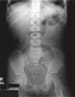

-

Abdominal radiographs confirm acute colonic pseudo-obstruction after hip surgery. Note extensive, diffuse colonic dilation with no evidence of transition point.